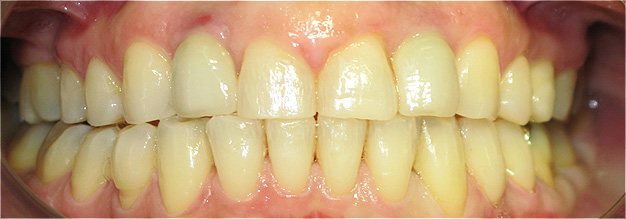

Apinhamento dentário com os dentes caninos em desoclusão (classe II, divisão 2).

![]() |

Após dois anos de tratamento ortodôntico.